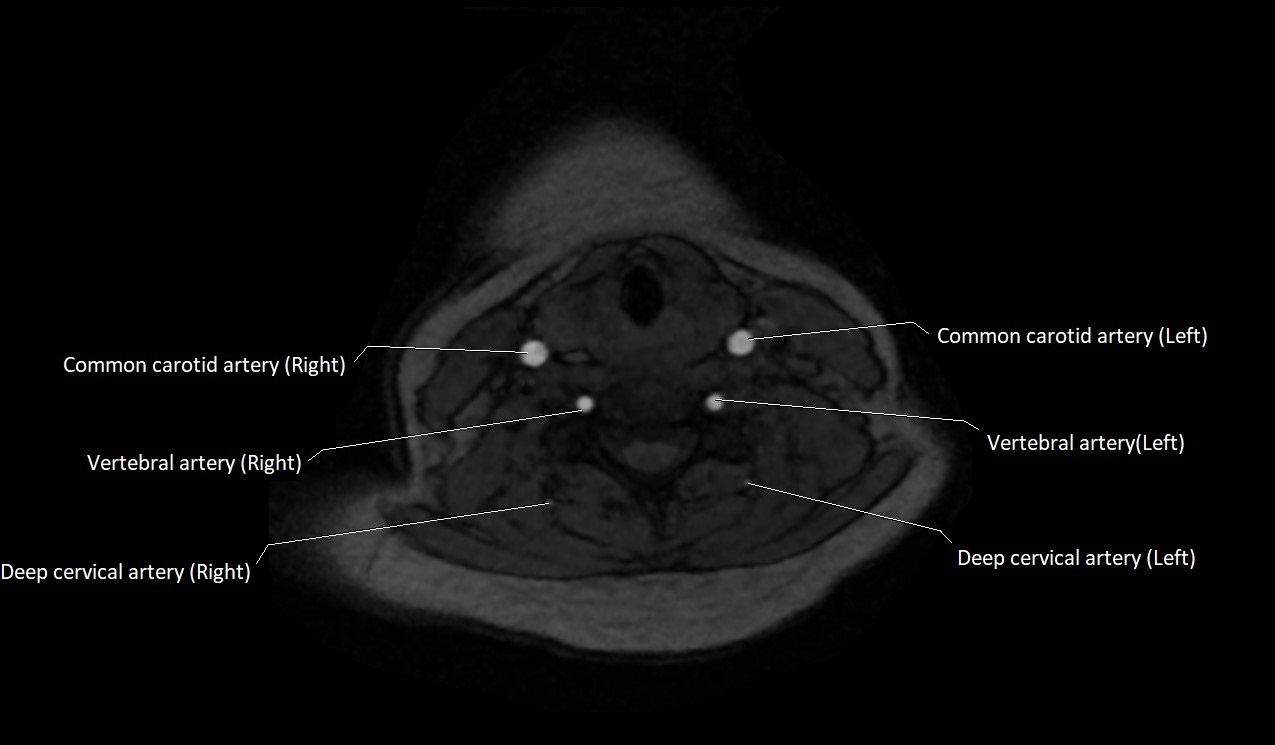

MRI images

image